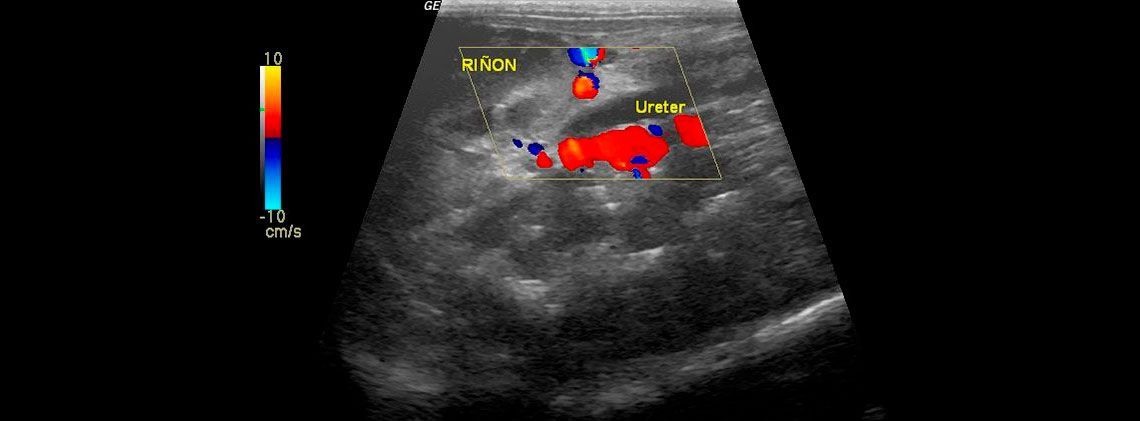

La ecocardiografía es una herramienta imprescindible en el diagnóstico y seguimiento de las patologías cardíacas, tanto congénitas como adquiridas, ya que nos permite visualizar el interior de corazón, pudiendo observar sus paredes, sus válvulas y aportando datos objetivos sobre la funcionalidad cardíaca. Además la ecocardiografía Doppler, (Doppler espectral, pulsado y continuo, y Doppler de flujo color) permite la evaluación de la dirección y la velocidad del flujo sanguíneo a traves del corazón y de los grandes vasos.